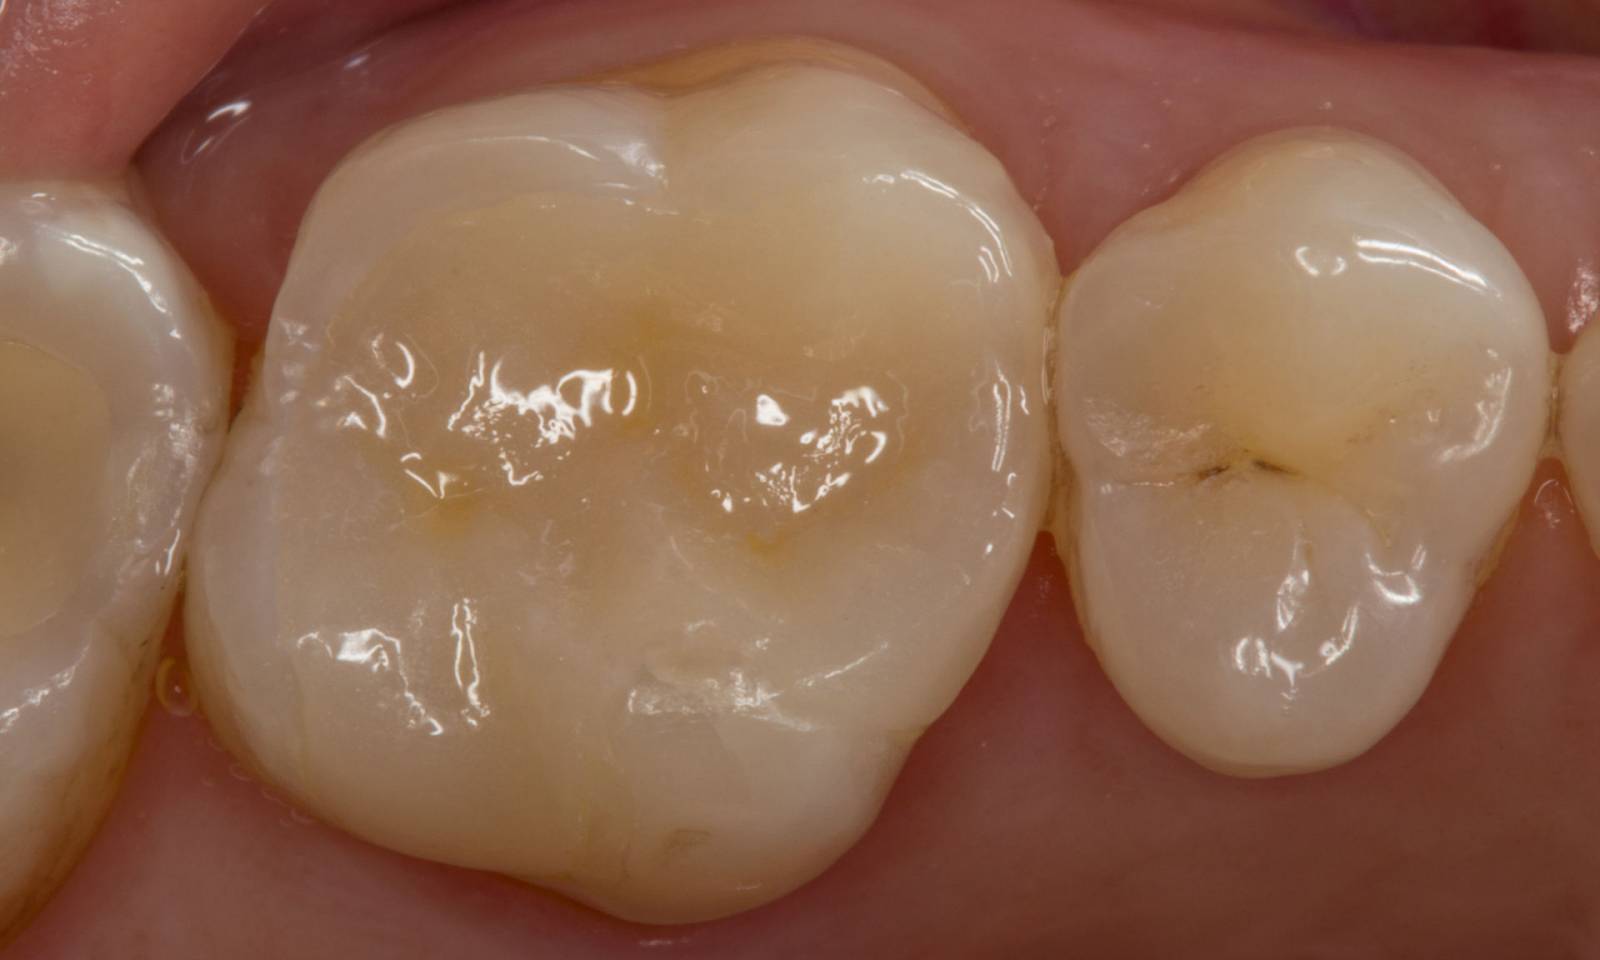

Before

A large carious mesial lesion on tooth 15. The tooth showed asymptomatic apical periodontitis and a significant loss of tooth structure.

After

Chairside-fabricated restoration made of CEREC MTL Zirconia designed using the Biogeneric individual function in the CEREC Software.